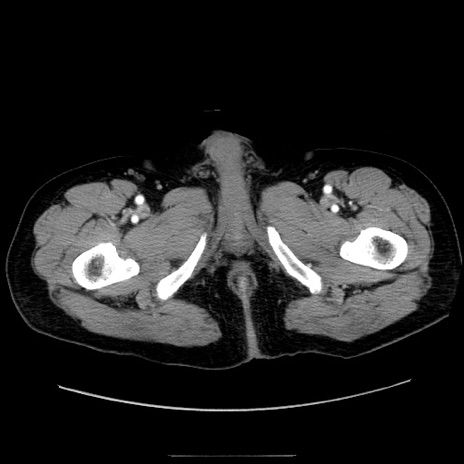

症例30(横断像)

【症例】80歳代男性

【主訴】臍周囲痛

【現病歴】約6時間前から臍下部痛が出現。次第に腹部膨隆・背部痛も生じてきたため来院。背部痛の場所は変化しない。

【既往歴】腎盂腎炎

【身体所見】意識清明、BT 36.3℃、BP  131/87mmHg、P 87bpm、SpO2 100%(RA)、臍周囲自発痛・圧痛あり、反跳痛なし、自発痛部位に一致して板状硬あり、腹部膨隆、腸雑音減弱、CVA tenderness両側陰性。

【データ】WBC 19600、CRP 0.33